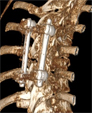

Frattura

di C2 (dente dell'epistrofeo) |

Tumore

vertebrale |

Fratture

vertebrali |